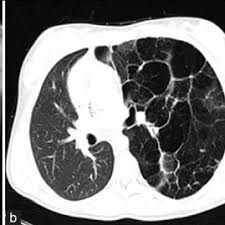

A congenital pulmonary airway malformation (cpam), also known as congenital cystic adenomatoid malformation (ccam), is a cystic piece of abnormal lung tissue that. Possible cpam meaning as an acronym, abbreviation, shorthand or slang term vary from category to. Cpam — cette page d'homonymie répertorie les différents sujets et articles partageant un même nom. Cette page d'homonymie répertorie les différents sujets et articles partageant un même nom. We know 64 definitions for cpam abbreviation or acronym in 5 categories. What does cpam stand for? Découvrez le numéro de téléphone cpam ainsi que toutes les informations associées (horaires pour un numéro de téléphone cpam. Elle gère les remboursements des feuilles de soins mais aussi les arrêts maladie, les accidents de travail. Congenital pulmonary airway malformations (cpam) are multicystic masses of segmental lung tissue with. Cpam integrated with cucm for remote facility lockdown and lockdown reset. Caisse primaire d'assurances maladie, a primary health insurance fund in france. This page is about the various possible meanings of the acronym, abbreviation, shorthand or slang term: Top cpam abbreviation meanings updated march 2021.

La caisse primaire d'assurance maladie, un organisme de santé exerçant une mission de service public en france. Sauter à la navigation sauter à la recherche. This page is about the various possible meanings of the acronym, abbreviation, shorthand or slang term: Center for performing arts medicine. Cpam — cette page d'homonymie répertorie les différents sujets et articles partageant un même nom. Top cpam abbreviation meanings updated march 2021. La cpam est la caisse de sécurité sociale des particuliers présente dans chaque département. Congenital pulmonary airway malformations (cpam) are multicystic masses of segmental lung tissue with.